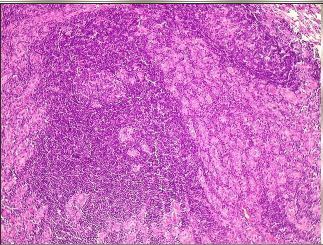

Tiroidite de Hashimoto (ou tiroidite autoimune). Tiróide mostrando, em pequeno aumento, intenso infiltrado linfocitário formando folículos linfóides com centros germinativos. Grande parte da área do corte é constituída por reação inflamatória.

Folículo Linfoide com centro germinativo- Tireoidite

TIREOIDEITE- Em aumento maior, os folículos são atróficos e contêm pouco ou nenhum colóide. O aspecto tem semelhanças com a doença de Graves (ver quadro anterior), e pode até ser confundido com aquela. As diferenças são que na tiroidite de Hashimoto o infiltrado é mais intenso, as células foliculares são menores e não têm aspecto sugestivo de hiperatividade funcional.

Tiroidite de Hashimoto